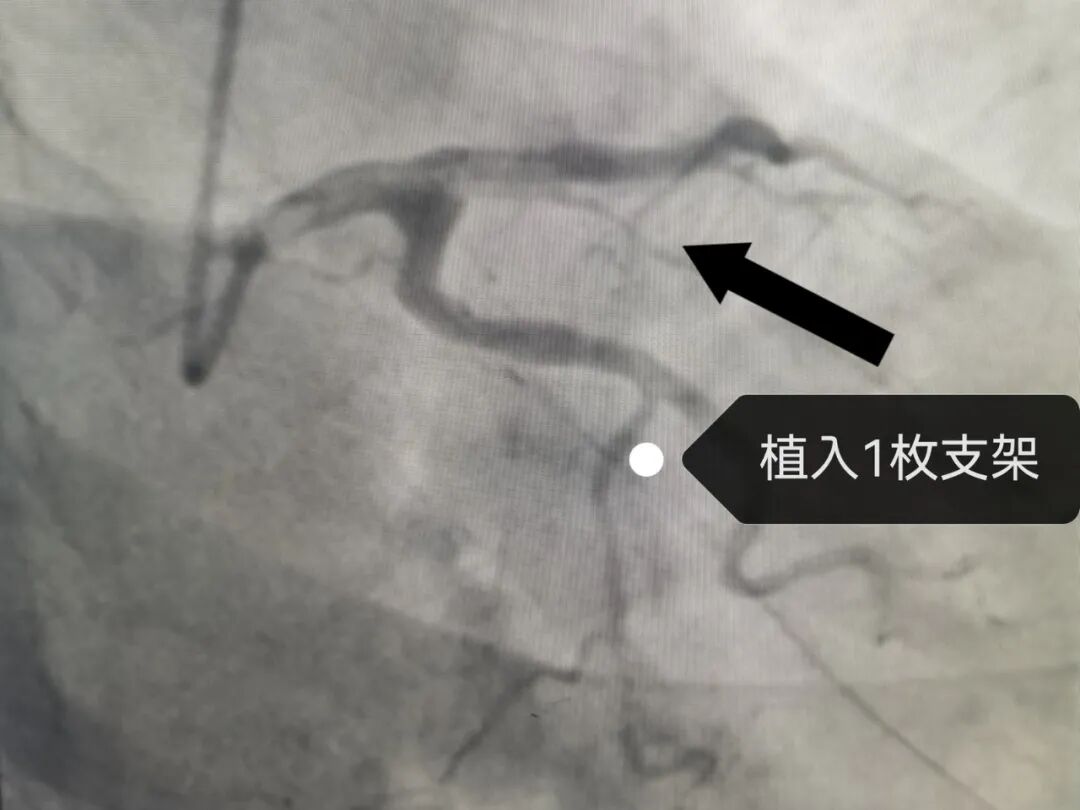

介入手术中,患者病情再次波动,突发室颤!手术团队沉着应对,紧急实施2次电除颤迅速恢复心律。冠脉造影结果显示:患者前降支近段完全闭塞,这是引发致命风险的“元凶”。心内科介入团队精准操作、快速开通血管,成功植入1枚支架,闭塞血管即刻恢复血流,患者胸痛症状消失,生命体征趋于平稳,手术圆满成功。